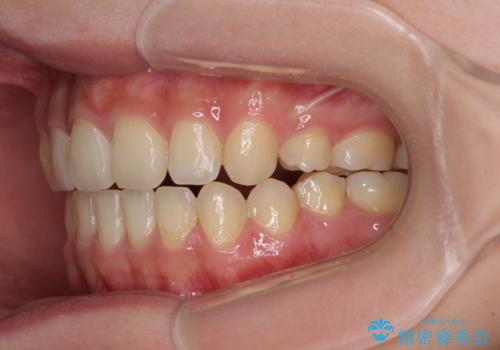

話しにくいオープンバイト ワイヤー装置による抜歯矯正治療

- 前歯のオープンバイトを気にして来院された患者様です。

上下前歯の前後位置が大きくずれていたため、上顎左右第一小臼歯2本を抜歯してワイヤー装置による矯正治療を行うこととしました。